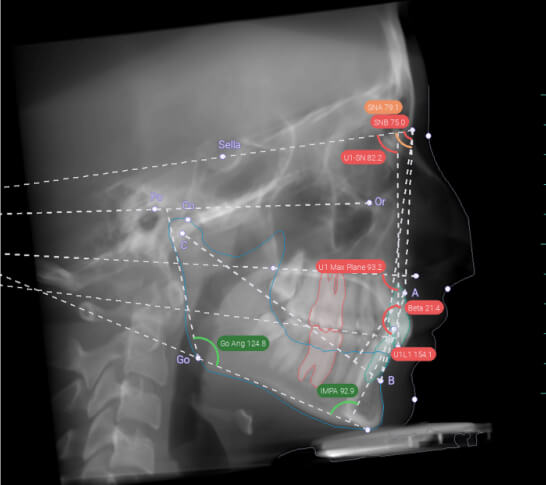

Особенно полезен алгоритм в ортодонтическом лечении. Программа помогает врачу рассчитать диагностические данные (углы, наклоны зубов, расположение челюстей относительно друг друга, основание черепа и т.д.), по которым ортодонт составляет план будущего лечения. Diagnocat помогает врачу-ортодонту выявить скрытые патологии зубов и скрытые скелетные формы. С помощью алгоритма можно просчитать, сколько места нужно сформировать для того, чтобы выровнять зубные ряды. Diagnocat определяет тип скелетного роста пациента. Эта информация нужна врачу для принятия решения об удалении отдельных зубов или об установке ортодонтических мини винтов.